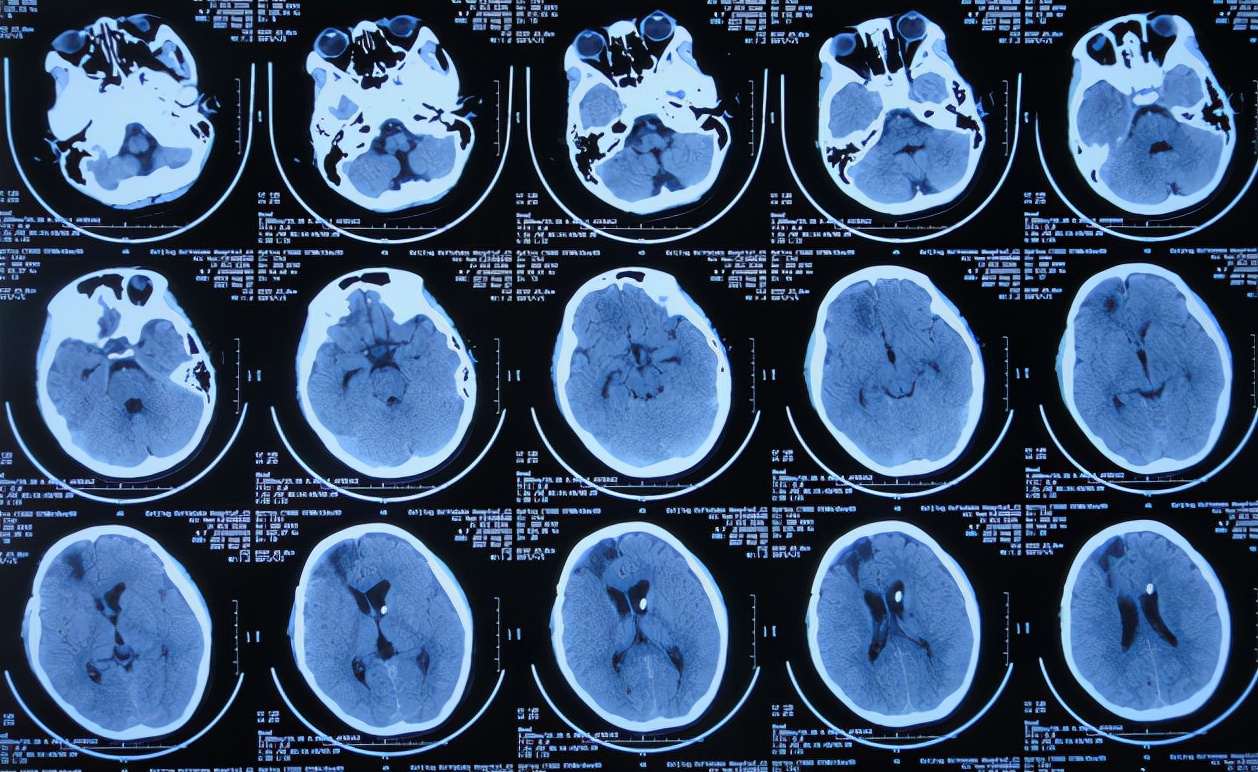

患者2021年3月23日早起突发头痛,意识不清,急送至江苏省徐州市睢宁县某医院,查脑CT示脑出血( 图-1 );既往史有癫痫病史。

图-1: 2021年3月23日脑CT

次日即2021年3月24日,转入该院的神经外科,仍发热体温高达38.0-39.0℃,查脑CT示出现水肿,仍有出血( 图-3 ),给予抗感染治疗。

图-3: 2021年3月24日脑CT